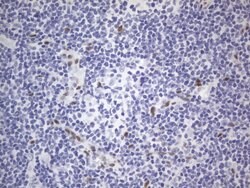

RBFOX1 Mouse anti-Human, Clone: OTI4F9, lyophilized, TrueMAB™

| Immunohistochemistry (Paraffin), Western Blot | |